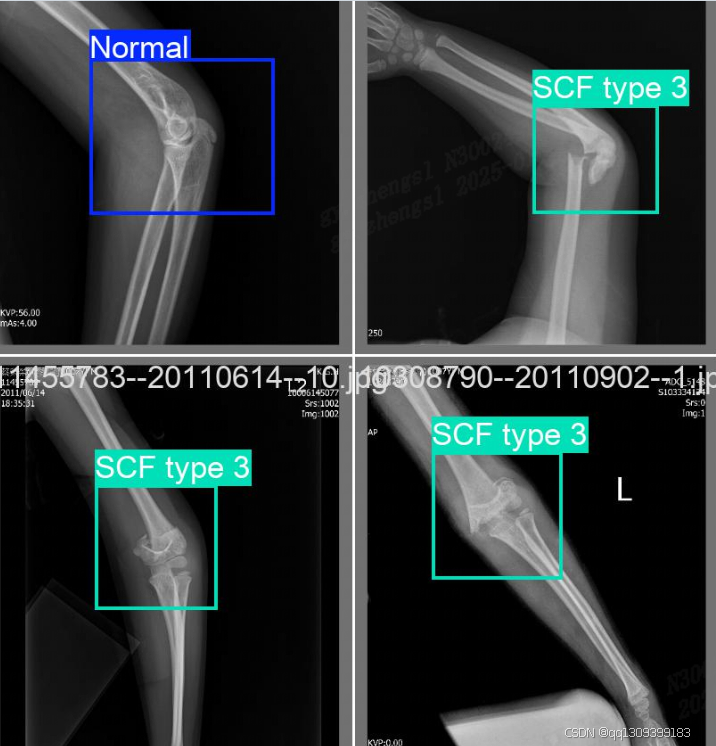

结果展示